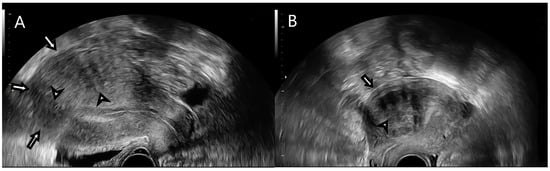

2.2. Ultrasound Examination

2.3. Strain Ratio Elastography Analysis